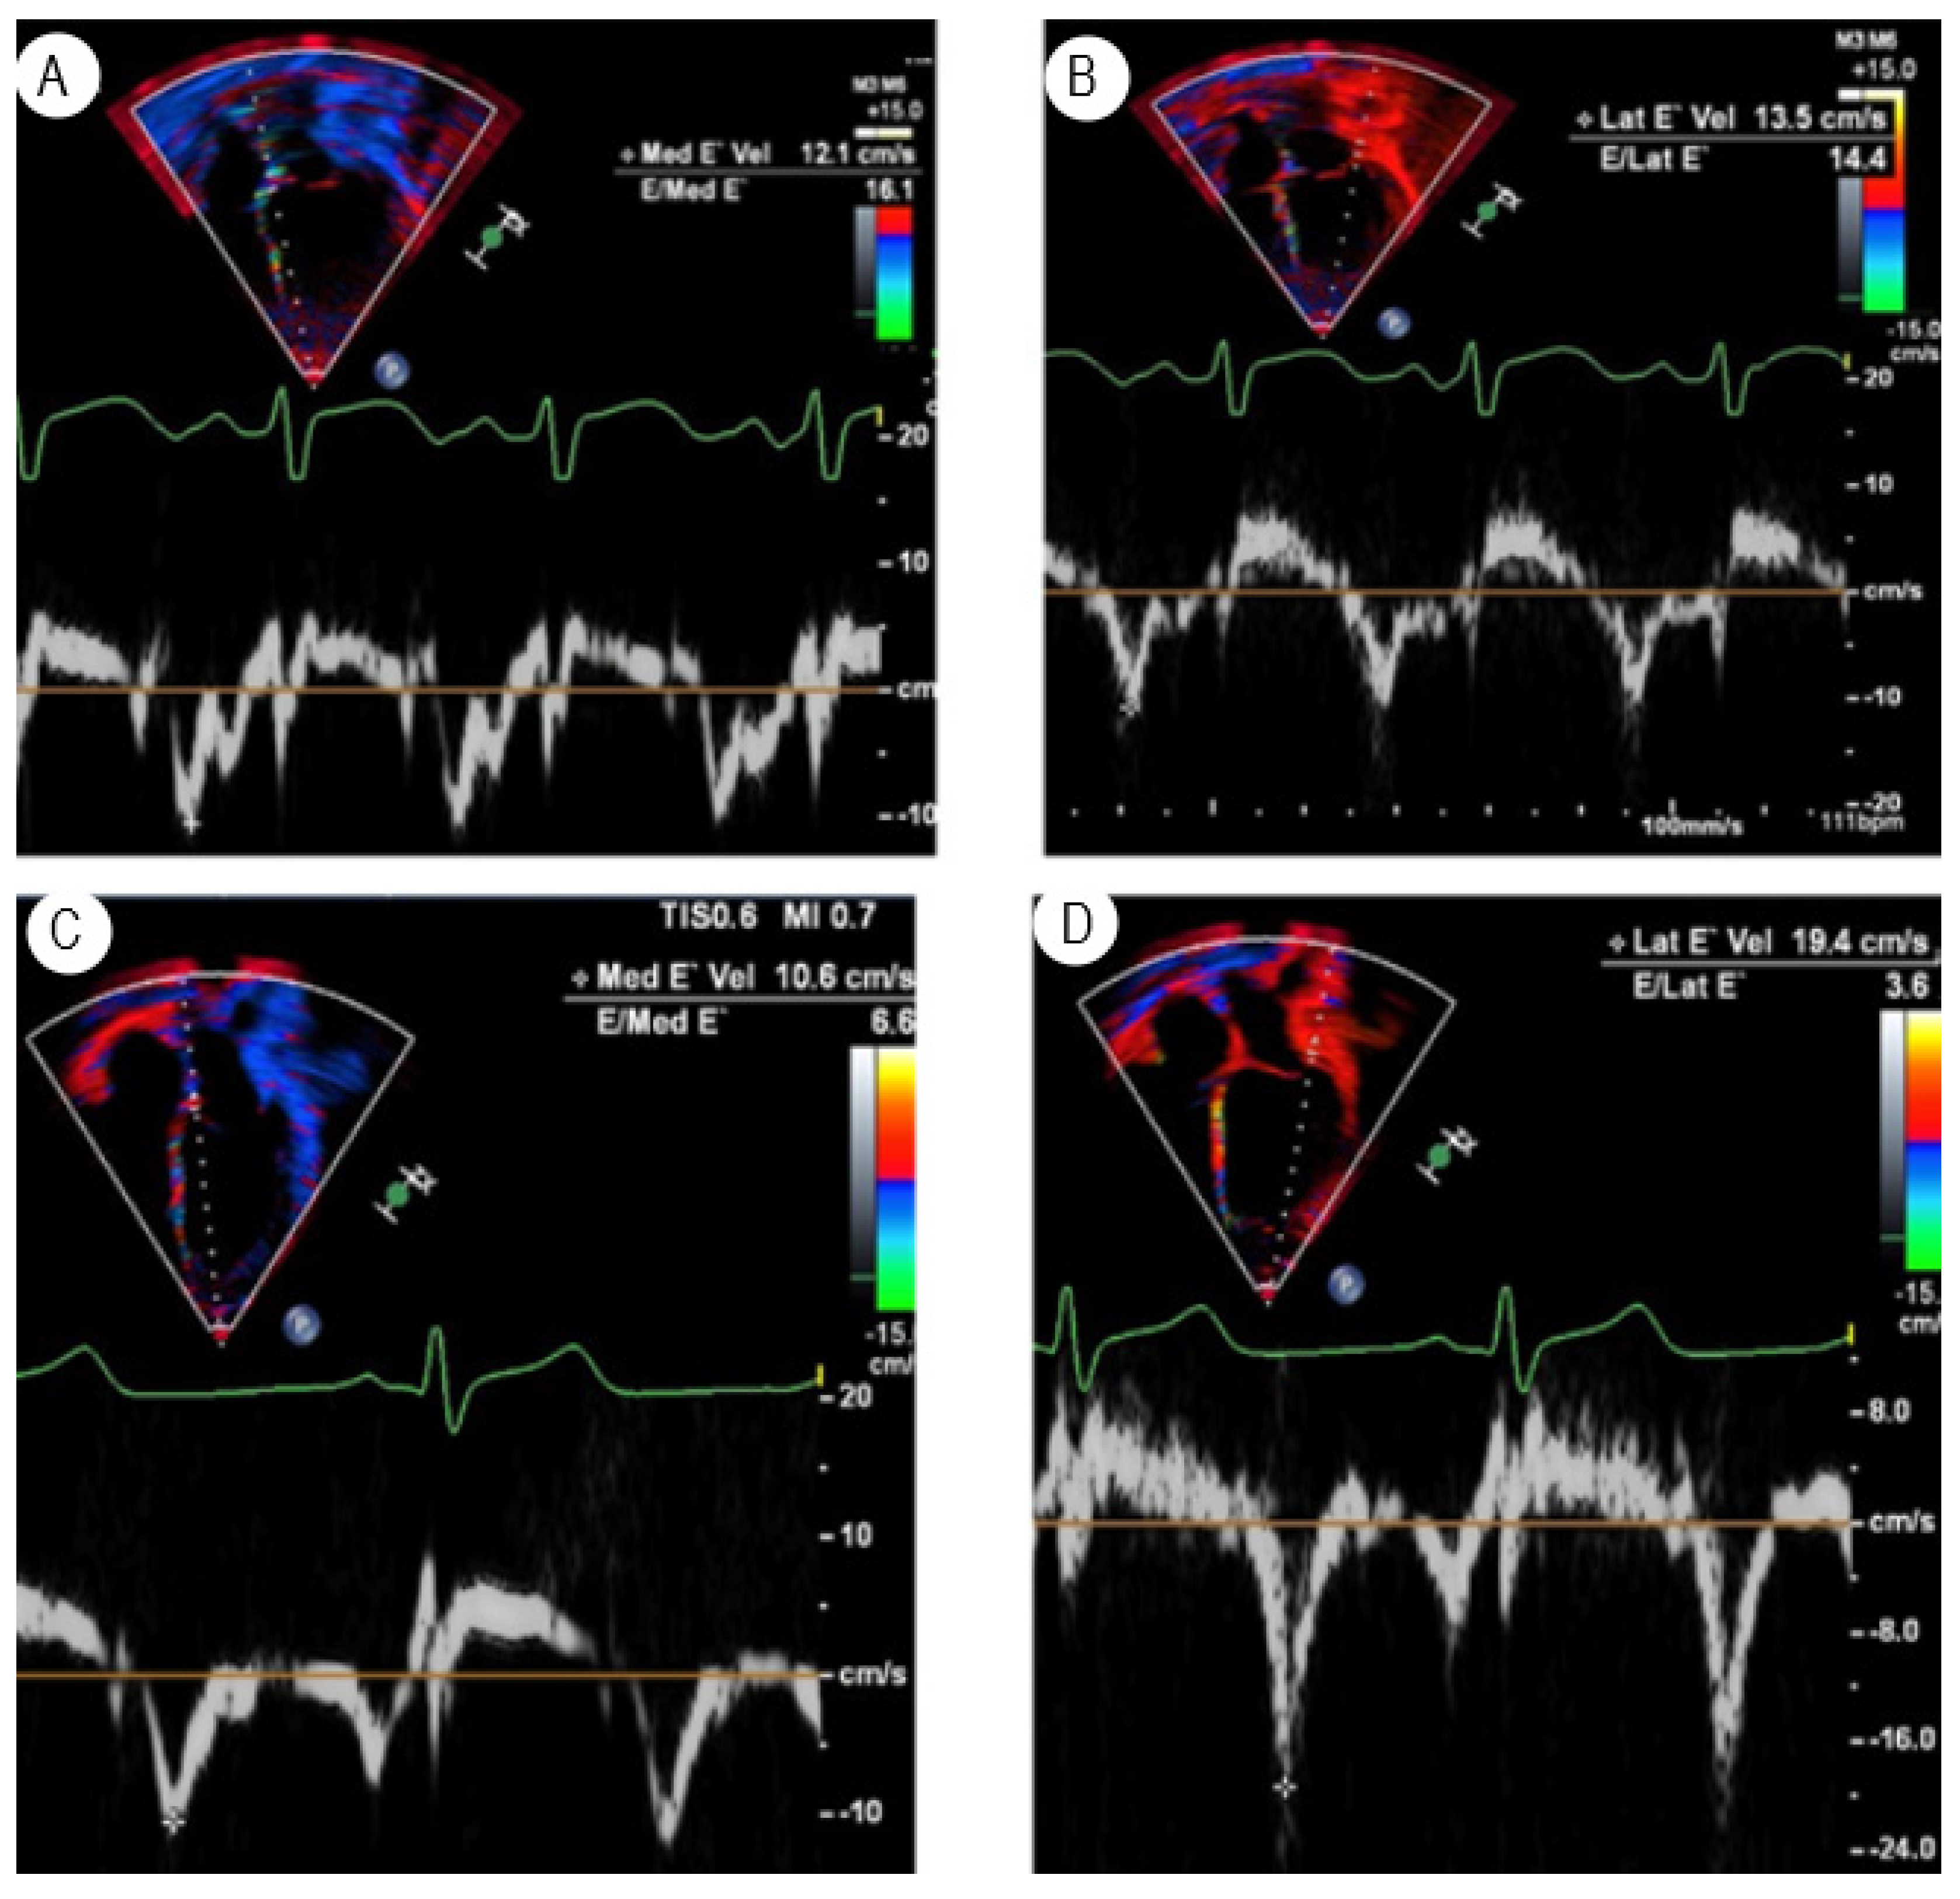

3.1. Tissue Doppler Imaging

- Hernandez, L.E.; Shepard, C.W.; Menk, J.; Lilliam, V.C.; Ameduri, R.K. Global left ventricular relaxation: A novel tissue Doppler index of acute rejection in pediatric heart transplantation. J. Heart Lung Transpl. 2015, 34, 1190–1197. [Google Scholar] [CrossRef]

- Hernandez, L.E.; Chrisant, M.K.; Valdes-Cruz, L.M. Global Left Ventricular Relaxation: A Useful Echocardiographic Marker of Heart Transplant Rejection and Recovery in Children. J. Am. Soc. Echocardiogr. 2019, 32, 529–536. [Google Scholar] [CrossRef] [PubMed]